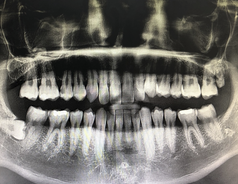

구강암은 입술, 혀, 입술 내부, 치은, 무치성 부위 등에서 발생할 수 있는 암 종류 중 하나입니다. 초기에는 통증이나 불편감이 느껴지지 않아 진단이 어렵기 때문에, 정기적인 구강 검진이 중요합니다. 그러나, 다음과 같은 초기증상이 발견된다면 구강암 의심이 있으므로, 신속하게 의료진과 상담해야 합니다.

구강암의 초기 증상은 다양하게 나타날 수 있으며, 발견 시 즉시 전문의와 상담하여 진단 검사를 받는 것이 중요합니다. 또한, 구강 검진은 정기적으로 받는 것이 좋습니다.